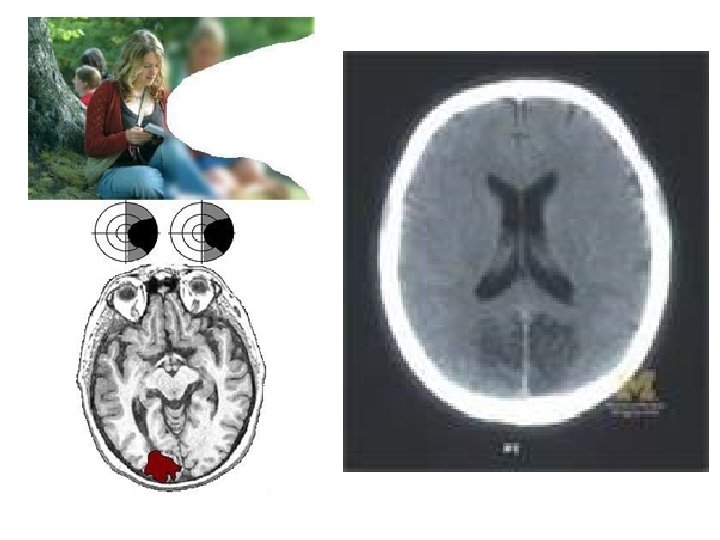

Optic Neuritis • Typically affects one eye of young women • Vision progressively dims over 48 hours (not truly "sudden") • Ache around eye at onset (worse with eye movement) • Reduced acuity and colour vision • A relative afferent pupil defect (RAPD) is present

Optic Neuritis • Fundus may be normal (retrobulbar neuritis) • Recovery over 6 weeks, more rapid if IV methylprednisolone. • Strong association with MS (MRI Brain will help predict risk)